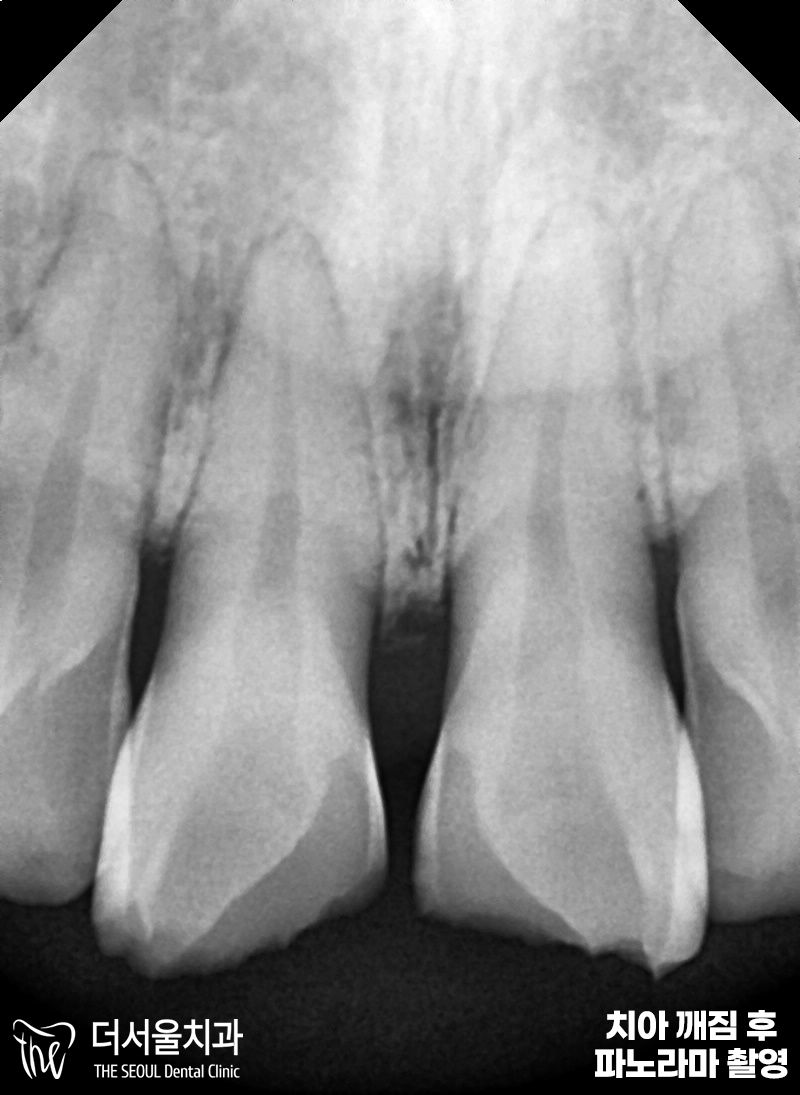

앞니가 깨졌을 때 곧바로 오셨던

첫 내원 당시인데요.

이가 완만한 곡선 형태로

깨져있는 것을 확인할 수 있습니다.

파노라마 엑스레이 촬영을 통해

좀 더 정밀 검사를 진행했습니다.

다행스럽게도 뿌리 근처까지 깨지지 않아서

큰 문제가 되는 상황은 아니었습니다.